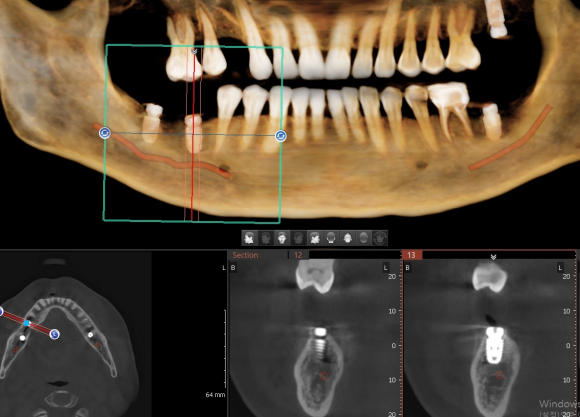

인천에서 오신 분 내과 당일 협진으로 전신 질환 (당요 등등) 확인 후 임플란트 식립. 뼈가 좋지 않아서 충분하게 분석 후 신경 손상을 피하기 위해 전략적이로 보수적으로 접근. 수술 후 3D 사진을 이용한 확인 완료. #상도동에서임플란트가장많이하는치과, #숭실대치과, #상도동치과, #동작구치과, #임플란트,...

인천에서 오신 분 내과 당일 협진으로 전신 질환 (당요 등등) 확인 후 임플란트 식립.

뼈가 좋지 않아서 충분하게 분석 후 신경 손상을 피하기 위해 전략적이로 보수적으로 접근.

수술 후 3D 사진을 이용한 확인 완료.